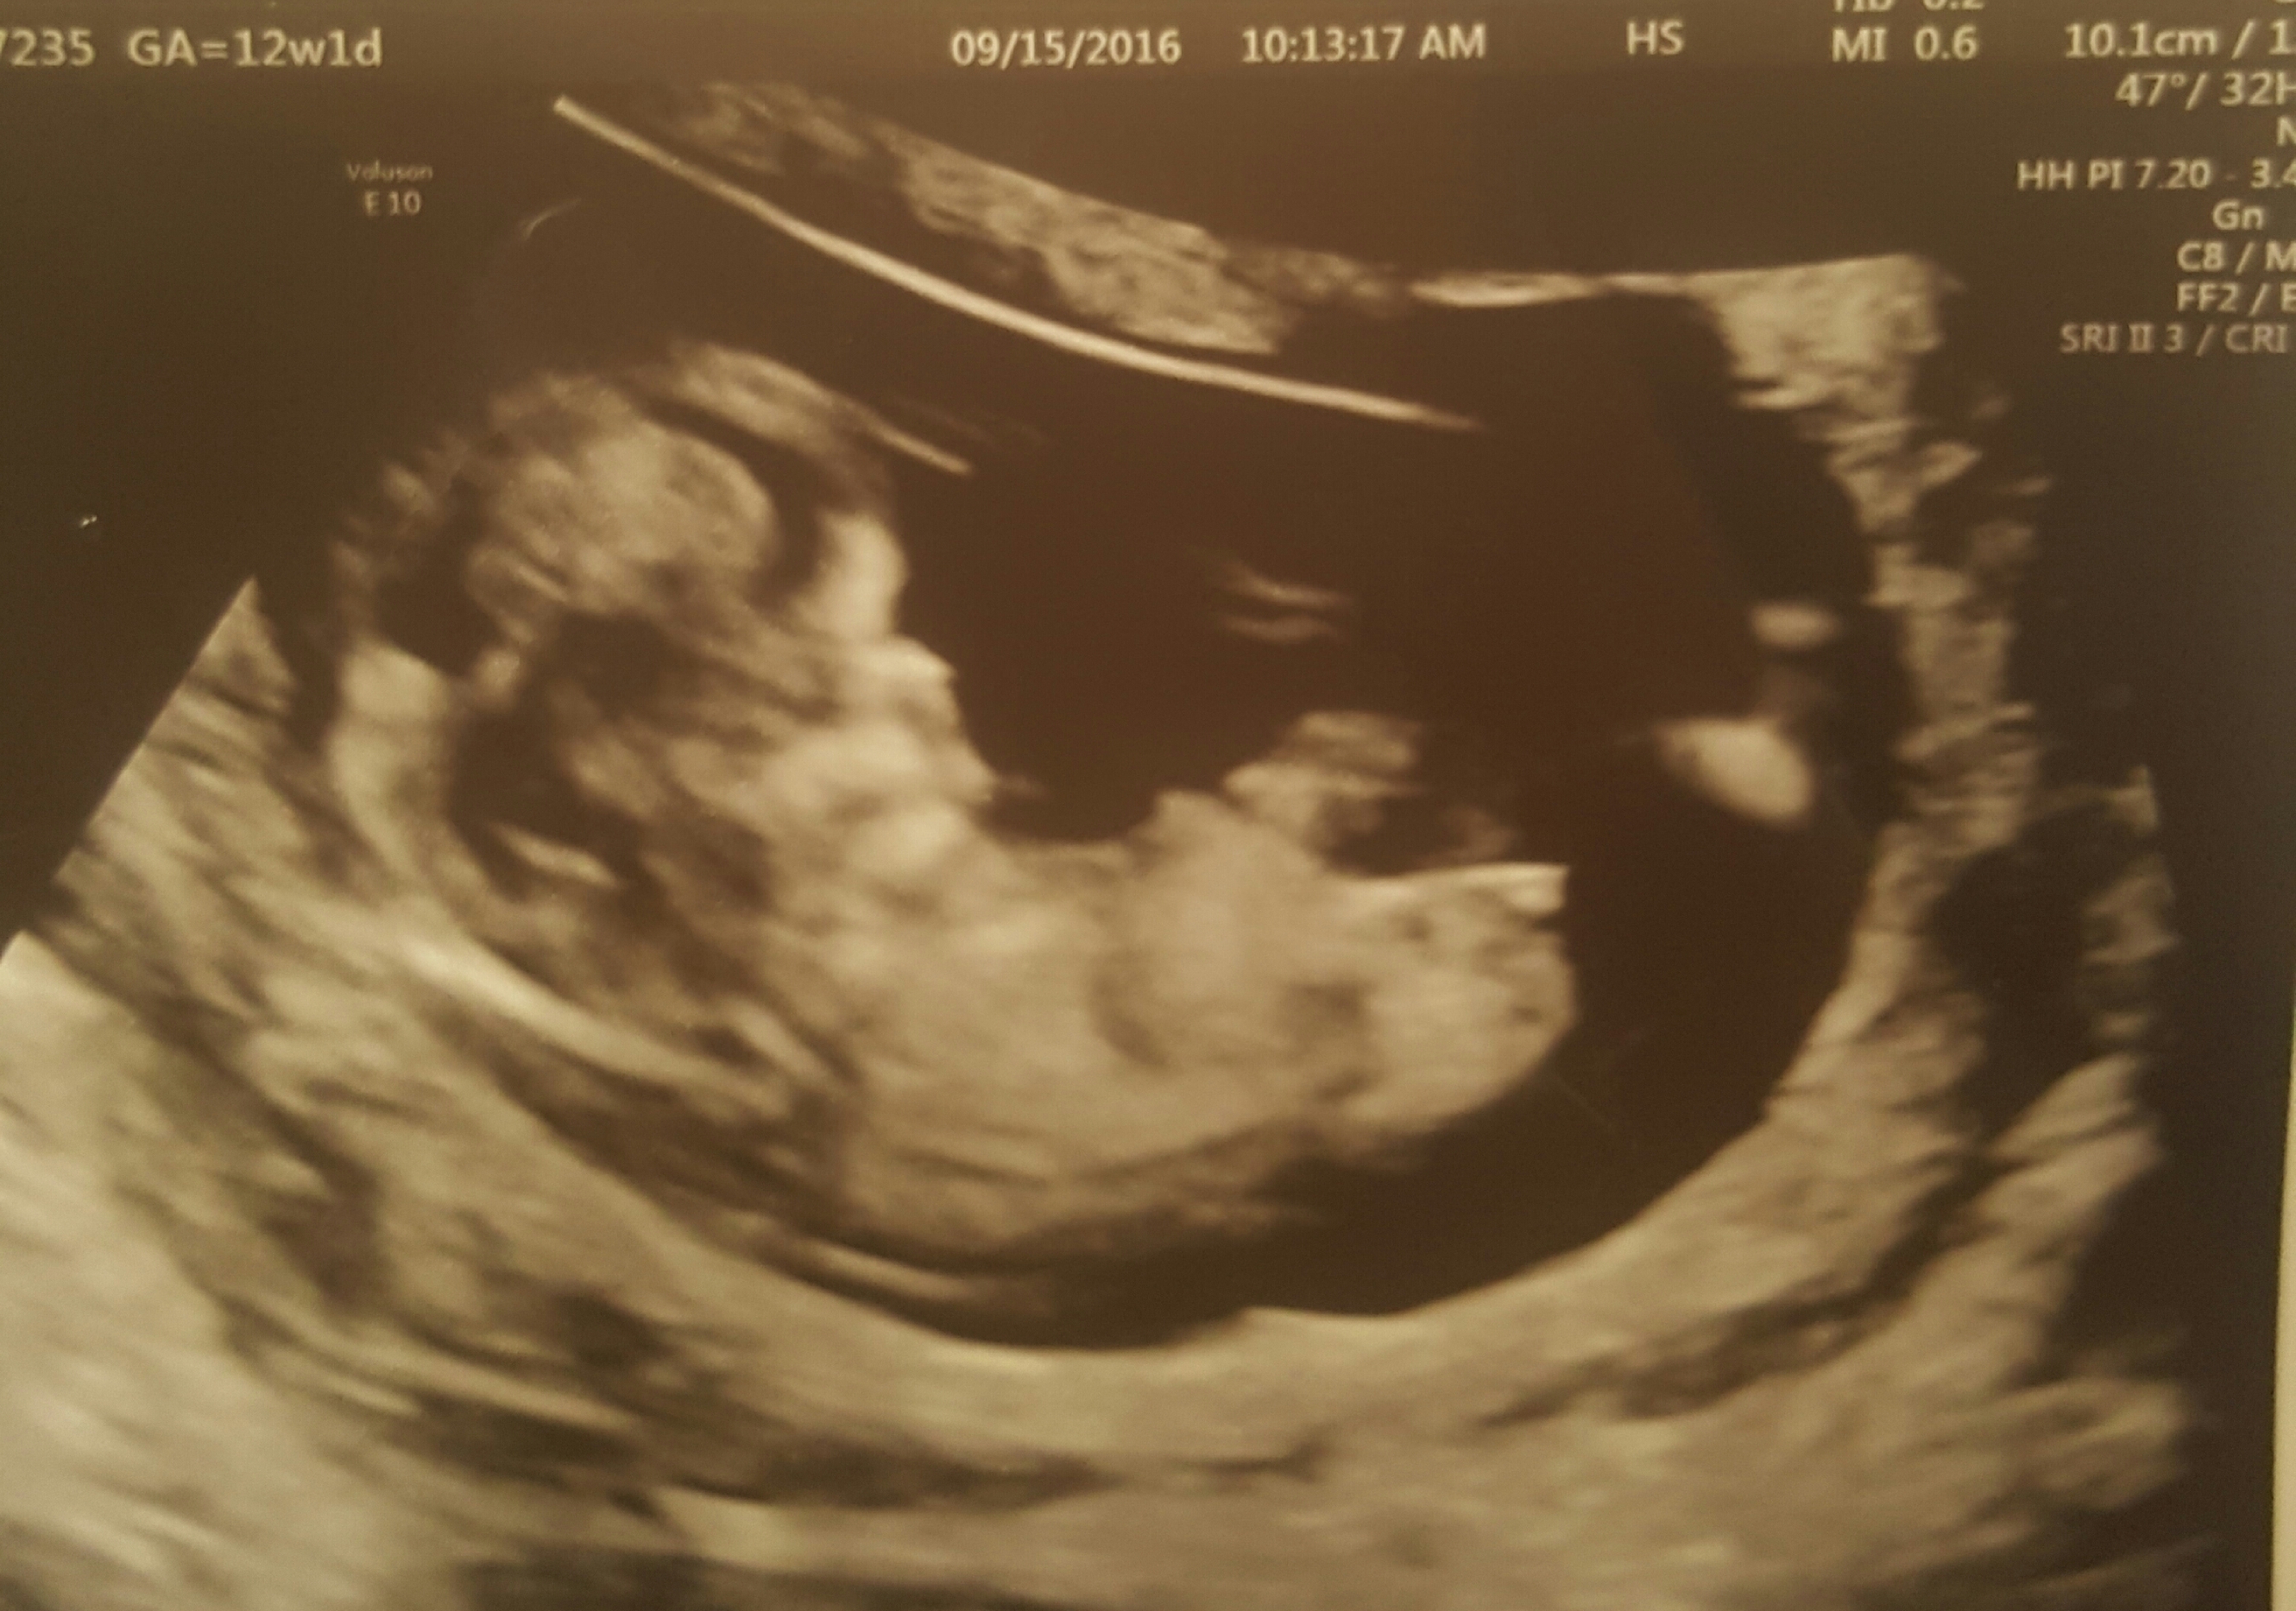

Sonograpgher says its too early so I don't know. Can someone help calm my anxiety? I have to wait until my 20 week sono and that's too long

It is really early. But I MIGHT be seeing a girl nub. Sorry that's not much help, but it's just too hard to give a sure answer so early.